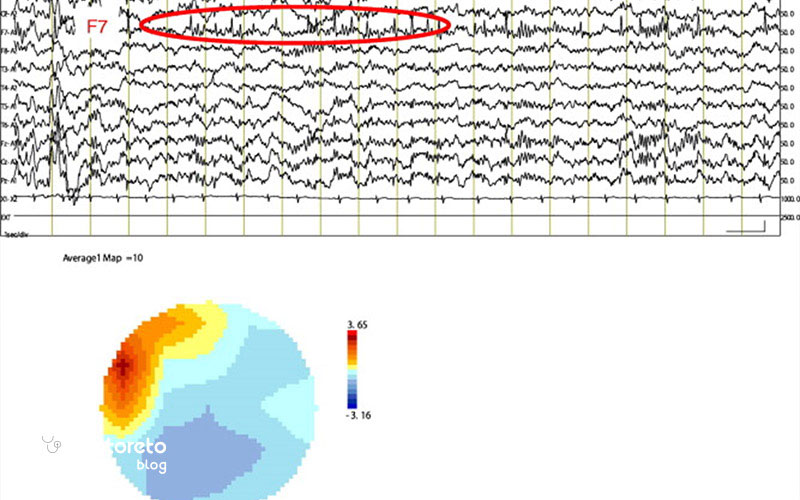

نوار مغزی یا EEG آزمایشی است که فعالیت الکتریکی مغز را ثبت میکند و برای تشخیص صرع، اختلال خواب، تومورها و سایر بیماریهای مغزی کاربرد دارد. این روش غیرتهاجمی است، جریان الکتریکی به بدن وارد نمیکند و معمولاً بدون درد انجام میشود. EEG میتواند هم در حالت بیداری و هم خواب انجام شود. پزشکان از نتایج این آزمایش برای کمک به تشخیص بیماری و انتخاب درمان مناسب استفاده میکنند. در عین حال ایمن بودن این روش، برخی بیماران عوارض بعد از نوار مغز را به صورت خفیف یا گذرا تجربه میکنند. آگاهی از این عوارض به کاهش نگرانی بیمار و تجربه راحتتر آزمایش کمک میکند. در ادامه این مقاله از دکترتو درباره خطرات نوار مغز بیشتر صحبت میکنیم.

در بیماران مبتلا به صرع، محرکهای EEG مانند نور چشمکزن یا هیپرونتیلاسیون میتوانند تشنج ایجاد کنند اما در افراد بدون سابقه بسیار نادر است. این وضعیت تحت کنترل دقیق کادر پزشکی رخ میدهد و اطلاعات مفیدی برای تشخیص نوع و محل تشنج ارائه میکند. با این حال، در افراد بدون سابقه صرع، وقوع تشنج بسیار نادر است.